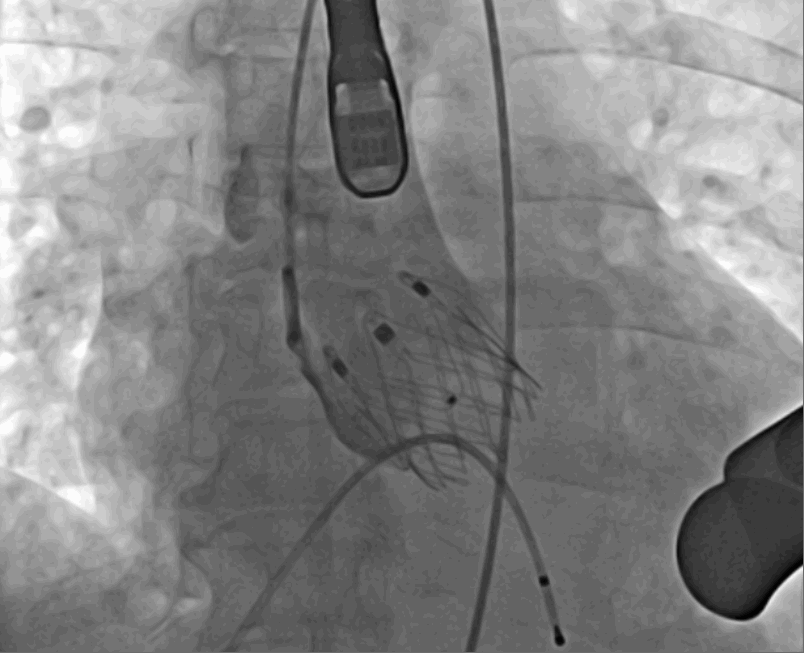

術(shù)前DSA影像圖

術(shù)中釋放定位鍵后DSA影像圖

術(shù)中瓣膜釋放過程

術(shù)后DSA影像